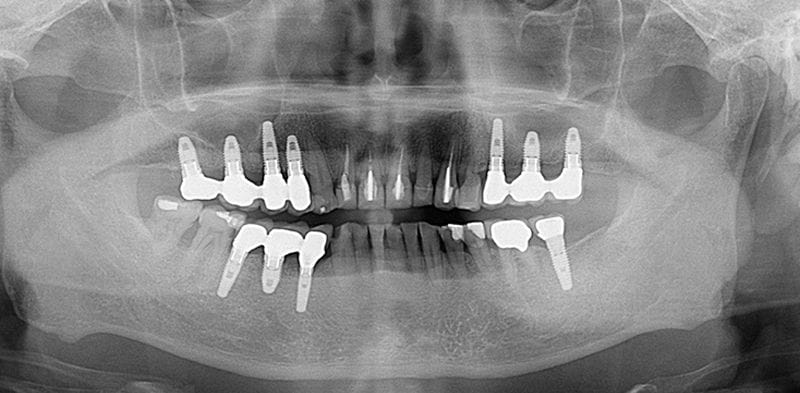

術後X光片